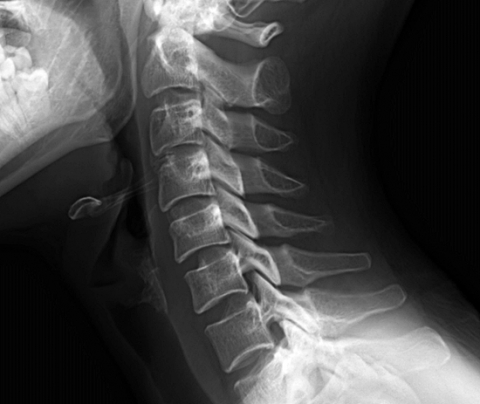

그러던 중 계속해서 몰려오는 피로와 어깨 통증 때문에 찾은 병원에서 스마트폰 증후군으로 인해 목디스크가 재발 했다는 이야기를 들었다. 이처럼 수술을 통한 디스크 치료의 경우 수술 후 재발의 위험이 있기 때문에 최근 척추관절 환자들 사이에서는 수술 없이 디스크와 척추관절 치료에 효과적인 추나요법과 카이로프랙틱이 인기를 얻고 있다.

추나요법과 카이로프랙틱은 비수술 요법으로 기계식 배드와 교정기구를 사용하여 틀어진 뼈와 근육을 정상적인 위치로 환원시킴으로 통증을 완화시키고 척추와 주변 조직의 기능을 원활하게 하는 치료법으로 디스크와 관절 질환에 좋은 효과를 보여 많은 사람들이 수술 외의 치료법으로 선호하는 가운데, 최근 비수술 치료 분야에 별다른 기구의 사용 없이 순수하게 손으로만 교정 치료를 시술해 효과와 정확도를 높인 경락척추교정술이 새로운 척추관절 치료법으로 주목을 받고 있다.

다소 생소한 이름의 치료법 경락척추교정술로 한방 치료의 차별화를 이루고 있는 척추 관절 전문 안양 해나라 한의원 한해 원장은 경락척추교정술에 대해 이렇게 전한다. “경락척추교정술은 기구를 쓰지 않고 순수하게 손으로만 교정하기 때문에 시술의 효과와 정확도가 높습니다. 또한 척추를 늘리고 풀어주기 때문에 척추 사이에 눌린 신경을 펴주게 하며 인대를 강화하는 효과 때문에 지속성이 뛰어납니다”